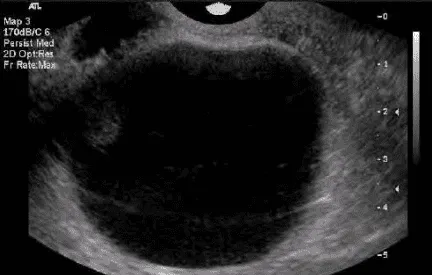

Phần tiêu đề “Nang noãn nang”Hình ảnh “Nang đơn trên siêu âm, 5-8 cm, thành mỏng, không chồi, không vách. Nang noãn nang thường tự mất sau vài chu kỳ”.

Là nang noãn không trưởng thành và không phóng noãn. Nang tiếp tục tăng kích thước, sản xuất steroid bất thường. Nguyên nhân do phản hồi steroid bị triệt tiêu (ví dụ dậy thì, quanh mãn kinh, steroid ngoại sinh, stress). Cấu trúc gồm thành lót tế bào hạt xung quanh tế bào vỏ, lòng nang chứa estrogen; Đôi khi chỉ còn tế bào vỏ nếu tế bào hạt tróc rời; Nang có thể đạt 5-8 cm, tồn tại xuyên chu kỳ.